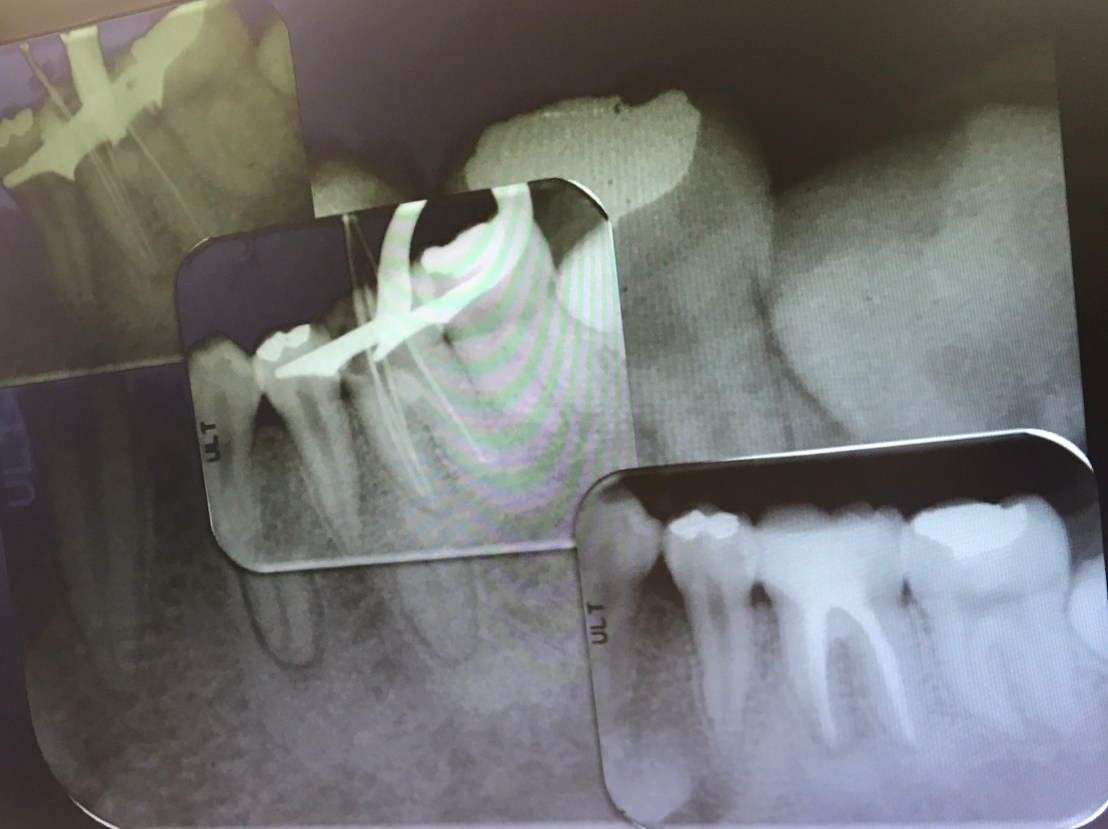

ฟัน #36, 46 คือฟันที่ท่านอาจารย์เตรียมไว้ให้สำหรับการฝึกการรื้อเครื่องมือและการซ่อมรอย perforate ในช่วงบ่าย

case แสดง Root canal retreatment ฟันซี่นี้มี Post หักที่ Distal root

การทำ Platform staging คือการทำให้เกิด Straight access ครับ

การเลือกใช้ Ultrasonic tip

แนวเส้นสีแดง คือ Coronal access

แสดงการเกิด space รอบๆ เครื่องมือที่หัก จากปลาย tip ของ ET20 ทำให้เกิด small groove